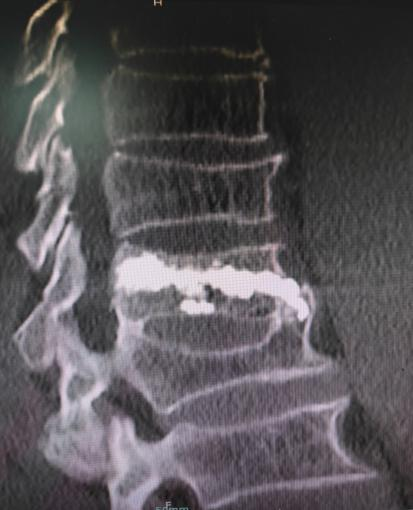

病例回顧 骨折部位 術(shù)中C臂協(xié)助定位 在C-臂監(jiān)視器透視下,分別定位胸12雙側(cè)椎弓根位置,標記穿刺點,僅以穿刺點為中心做3mm切開,在透視下注入骨水泥,再次透視見骨水泥位置良好。 骨水泥注入 術(shù)后影像學檢查 手術(shù)切口1cm左右 該手術(shù)經(jīng)皮透視下穿刺,手術(shù)切口小,創(chuàng)傷小,無需縫合,術(shù)后患者即感腰部疼痛明顯減輕,第二天可下床行走,已無腰痛不適,張大娘非常高興,自己再也不會受腰痛折磨整日與床為伴了。 我院脊柱骨科近年來,已成功開展多臺PVP手術(shù),為廣大老年患者減輕了病痛,減少了患者臥床時間,提高了生活質(zhì)量,是骨質(zhì)疏松性椎體骨折患者的福音。如果家里的老人突然出現(xiàn)了腰背疼痛,翻身下床困難,或者出現(xiàn)了腹部不適,排除腹部疾病(因為很多胸腰椎骨折患者在早期以腹痛腹脹為最主要癥狀),無論有沒有外傷史,建議帶老人及早就醫(yī),如果發(fā)現(xiàn)椎體損傷,積極治療,讓老人度過一個輕松愉快的晚年生活。 科普小講堂:經(jīng)皮椎體成形術(shù) 什么是骨質(zhì)疏松性椎體骨折? 骨質(zhì)疏松性椎體壓縮骨折,即在日常生活中患者并未遭受到明顯的外力而發(fā)生的骨折。這種骨折與創(chuàng)傷性的骨折不同,是由于自身骨質(zhì)疏松所導(dǎo)致的骨組織病變。骨質(zhì)疏松性骨折發(fā)生時,患者會感覺到背部明顯疼痛,翻身或起床等動作會讓疼痛更加明顯。 骨質(zhì)疏松性椎體壓縮骨折的危害有哪些? 一旦椎體發(fā)生骨質(zhì)疏松性椎體壓縮骨折,常常會導(dǎo)致患者出現(xiàn)腰背部持續(xù)性疼痛、季肋部放射痛、后凸畸形、呼吸功能受限及胃腸道癥狀等諸多癥狀,造成老年患者生活質(zhì)量下降。 什么是經(jīng)皮椎體成形術(shù)? (Percutaneousvertebroplasty,PVP)是一種新型的脊柱微創(chuàng)手術(shù),通過采用經(jīng)皮穿刺的方法,經(jīng)過椎弓根或是直接向椎體中注入骨水泥,使得椎體的強度和穩(wěn)定性得以提升,防止塌陷,從而達到緩解腰背疼痛,甚至部分恢復(fù)椎體高度的目的。 PVP手術(shù)優(yōu)點是什么? 1.恢復(fù)顯著:通常術(shù)后6個小時即能達到穩(wěn)定固定,患者可下床站立活動,大大縮短了患者臥床的時間。 2.疼痛減輕:術(shù)后患者會發(fā)現(xiàn)腰背部疼痛明顯減輕。 3.微創(chuàng):該治療方法僅需在皮膚上留2-3mm的穿刺針孔。 4.安全性:由于手術(shù)采用的是局部麻醉,因此即便是存在多種基礎(chǔ)病的患者也能夠耐受手術(shù),整個手術(shù)過程相對安全。 就診地址 酒泉市中醫(yī)醫(yī)院四樓脊柱骨科 咨詢電話 一樓門診部:0937-2669161 王醫(yī)生:13209409826 ??? 張醫(yī)生:18219971722